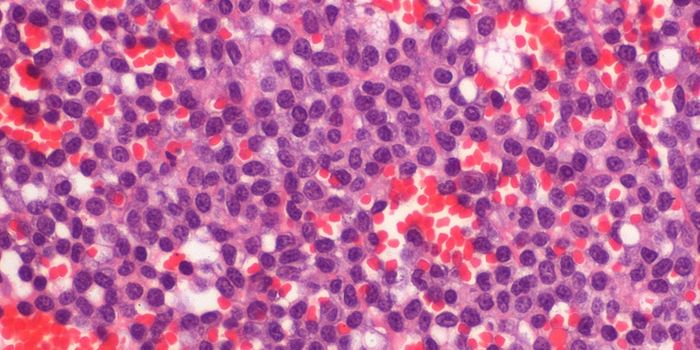

APR 30, 2016CancerResearchers recently reported that immunotherapy led to remission in 93 percent of patients with advanced leukemia. Thou ...